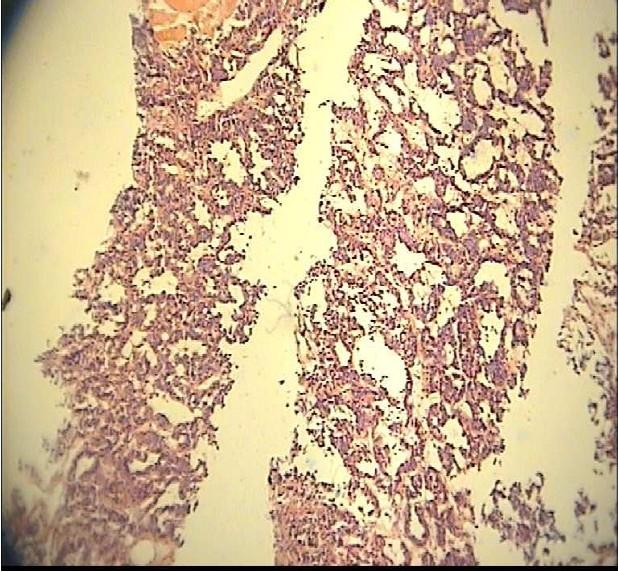

Ovarian sex cord-stromal tumors, including granulose cell tumors (GCTs), are a group of neoplasms that occur rarely, especially in children. Only 0.1 percent of all ovarian tumors and 4-5 percent of GCTs occur in children. The most common presentation of these tumors in children is precocious puberty. We report a 6 years old girl with isosexual precocity, presented as premature thelarche and vaginal bleeding. Ultrasonography of pelvis showed a hypoechoic solid mass of left ovary.Microscopic features of the resected mass were characteristic of juvenile GCT. Although in most of girls with precocious puberty, the etiology is idiopathic, important causes, such as ovarian tumors must be considered.

卵巢性索间质肿瘤,包括颗粒细胞瘤(GCTs),是一组罕见的肿瘤,尤其是在儿童中。在所有卵巢肿瘤中,只有0.1%发生于儿童,而颗粒细胞瘤在儿童中的发生率为4%-5%。这些肿瘤在儿童中最常见的表现是性早熟。我们报告一名6岁患同性性早熟的女孩,表现为乳房过早发育和阴道出血。盆腔超声检查显示左侧卵巢有一个低回声实性肿块。切除肿块的显微镜特征为青少年颗粒细胞瘤。虽然大多数性早熟女孩的病因是特发性的,但必须考虑重要病因,如卵巢肿瘤。